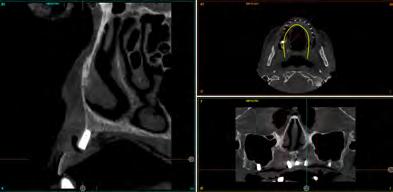

Fueron reclutados de forma retrospectiva, pacientes que presentasen atrofia ósea extrema mixta, tanto en maxilar como en mandíbula y en los que se insertasen implantes extracortos (5.5 y 6.5 mm) y de plataforma reducida de 3 mm, durante un periodo comprendido entre junio de 2020 y junio de 2021. Antes de la inserción de los implantes se utilizó una premedicación antibiótica consistente en amoxicilina 2 g vía oral una hora antes de la intervención y paracetamol 1 g vía oral (como analgésico). Posteriormente los pacientes prosiguieron con un tratamiento de amoxicilina 500-750 mg vía oral cada 8 horas (según peso) durante 5 días. Todos los pacientes fueron estudiados antes de la inserción de los implantes mediante modelos diagnósticos, exploración intraoral y realización de un TAC dental (cone-beam) analizado posteriormente mediante un software específico (BTI-Scan III).

Figura 8-11. Imágenes de la planificación del cone-beam dentral tras el cierre de los tejidos blandos (inserción temprana de los implantes). En ellos observamos la planificación de los implantes de 6.5 mm de longitud y de diámetro reducido y plataforma 3.0 que van a ser empleados.

Dentista y Paciente 18 Calidad y dirección